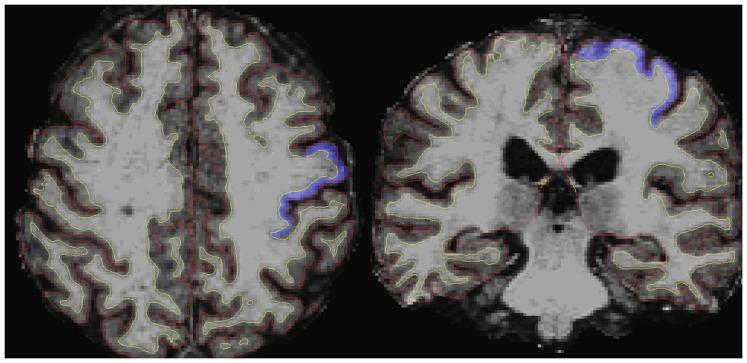

Amyotrophic lateral sclerosis (ALS) has heterogeneous clinical features that could be translated into specific patterns of brain atrophy. In the current study we have evaluated the relationship between different clinical expressions of classical ALS and measurements of brain cortical thickness. Cortical thickness analysis was conducted from 3D-MRI using FreeSurfer software in 29 ALS patients and 20 healthy controls. We explored three clinical traits of the disease, subdividing the patients into two groups for each of them: the bulbar or spinal onset, the higher or lower upper motor neuron burden, the faster or slower disease progression. We used both a whole brain vertex-wise analysis and a ROI analysis on primary motor areas. ALS patients showed cortical thinning in bilateral precentral gyrus, bilateral middle frontal gyrus, right superior temporal gyrus and right occipital cortex. ALS patients with higher upper motor neuron burden showed a significant cortical thinning in the right precentral gyrus and in other frontal extra-motor areas, compared to healthy controls. ALS patients with spinal onset showed a significant cortical thinning in the right precentral gyrus and paracentral lobule, compared to healthy controls. ALS patients with faster progressive disease showed a significant cortical thinning in widespread bilateral frontal and temporal areas, including the bilateral precentral gyrus, compared to healthy controls. Focusing on the primary motor areas, the ROI analysis revealed that the mean cortical thickness values were significantly reduced in ALS patients with higher upper motor neuron burden, spinal onset and faster disease progression related to healthy controls. In conclusion, the thickness of primary motor cortex could be a useful surrogate marker of upper motor neuron involvement in ALS; also our results suggest that cortical thinning in motor and non motor areas seem to reflect the clinical heterogeneity of the disease.

肌萎缩侧索硬化症(ALS)具有异质性的临床特征,这些特征可以转化为特定的脑萎缩模式。在本研究中,我们评估了不同临床表达的经典 ALS 与大脑皮质厚度测量之间的关系。皮质厚度分析是通过 3D-MRI 使用 FreeSurfer 软件在 29 名 ALS 患者和 20 名健康对照组中进行的。我们探讨了疾病的三种临床特征,将患者分为两组:延髓或脊髓发病、上运动神经元负担更高或更低、疾病进展更快或更慢。我们使用了全脑顶点分析和主要运动区的 ROI 分析。ALS 患者双侧中央前回、双侧额中回、右侧颞上回和右侧枕叶皮质变薄。与健康对照组相比,上运动神经元负担较高的 ALS 患者右侧中央前回和其他额外运动区的皮质变薄更明显。与健康对照组相比,脊髓发病的 ALS 患者右侧中央前回和旁中央小叶的皮质变薄更明显。进展较快的 ALS 患者双侧额、颞广泛区域皮质变薄更明显,包括双侧中央前回,与健康对照组相比。聚焦于主要运动区,ROI 分析显示,与健康对照组相比,上运动神经元负担较高、脊髓发病和疾病进展较快的 ALS 患者的皮质厚度平均值明显降低。总之,初级运动皮质的厚度可能是 ALS 中运动神经元受累的有用替代标志物;我们的结果还表明,运动和非运动区的皮质变薄似乎反映了疾病的临床异质性。